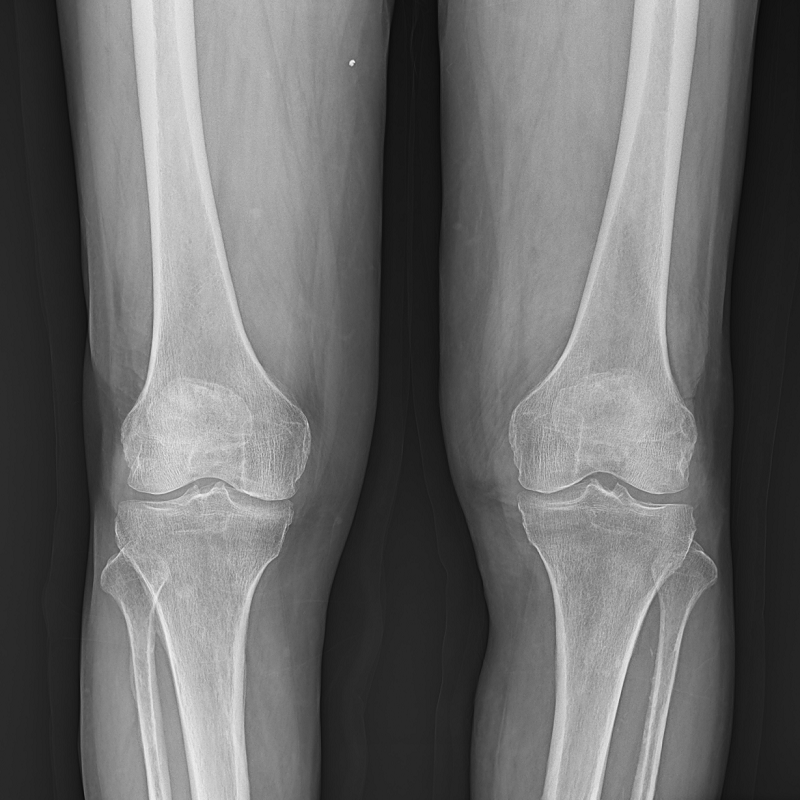

●呈現(xiàn)全下肢或全脊柱圖像

●在脊柱及下肢畸形矯正手術(shù)治療中,為術(shù)前方案制定和術(shù)后復(fù)查提供精準(zhǔn)測量

●有效解決傳統(tǒng)X光片不能一次成像問題,為患者提供更加優(yōu)質(zhì)的醫(yī)療服務(wù)